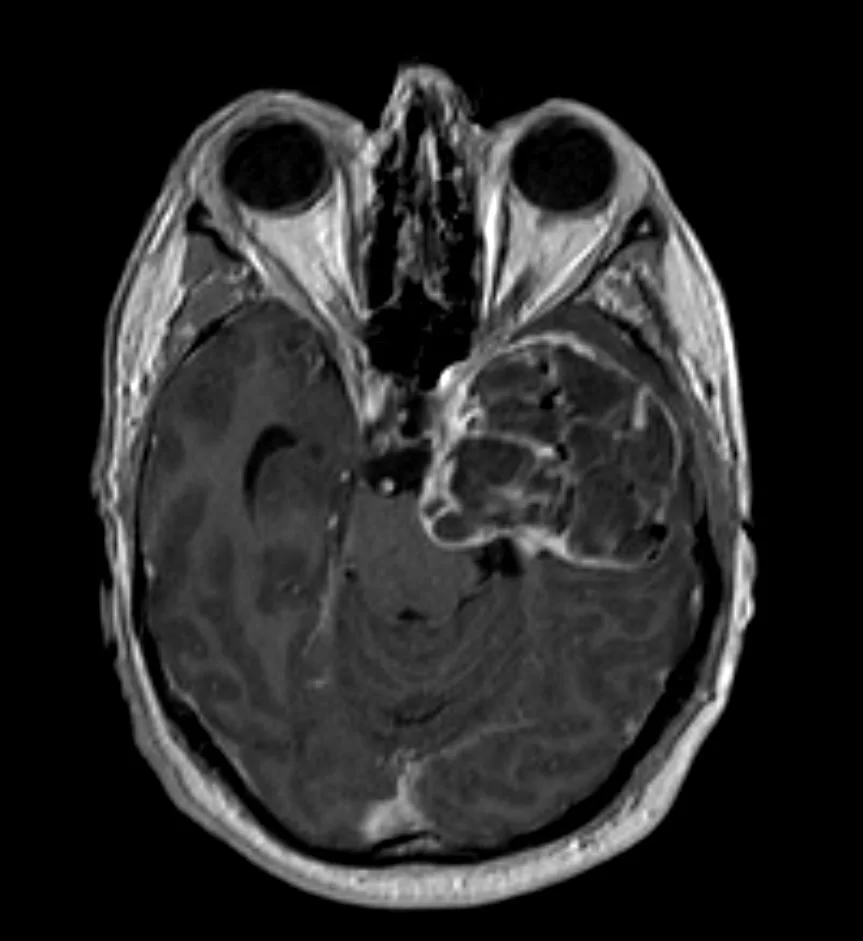

Μηνιγγίωμα γεφυροπαρεγκεφαλιδικής γωνίας δεξιά

Ασθενής άνδρας, 45 ετών με αιμωδίες του δεξιού ημιπροσώπου, ιλίγγους και κεφαλαλγία. Η μαγνητική τομογραφία εγκεφάλου ανέδειξε εκτεταμένη χωροκατακτητική εξεργασία

Περισσότερα